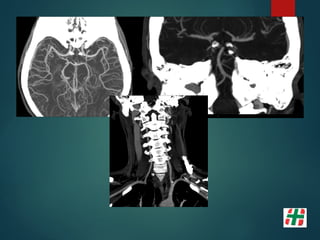

Disección Vascular

 Causa frecuente de Stroke isquémico en adultos jóvenes.

 Desgarro de la pared con formación de hematoma mural.

 Multifactorial, Trauma, infecciones, etc.

 Determinar extensión.

Mayor indicación de la secuencia TOF. Valor del crudo.

• 16.

Disección Vascular  Causafrecuente de Stroke isquémico en adultos jóvenes.  Desgarro de la pared con formación de hematoma mural.  Multifactorial, Trauma, infecciones, etc.  Determinar extensión.  Mayor indicación de la secuencia TOF. Valor del crudo.